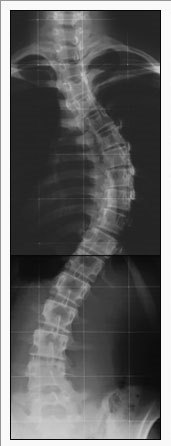

Well duh. I’ve been an exerciser most of my life, and I can’t imagine life without it. This is, I think, thanks to being diagnosed with scoliosis and having to wear a full body brace, 23 hours a day, for several years starting at age 12 or 13.

During the 24th hour, I could take a bath (not a shower) and do my physical therapy. The doctors and my mother warn me that if I didn’t do my PT I might have to have surgery to implant a metal rod alongside my spine. In retrospect I think surgery would have been easier, socially, than wearing a brace. It’s no fun being called “cripple girl.”

But guess what? Doing PT every day year after year created the habit of exercise. So that brace was good for something, because now the medical profession knows that bracing doesn’t have any lasting straightening effect on scoliosis.